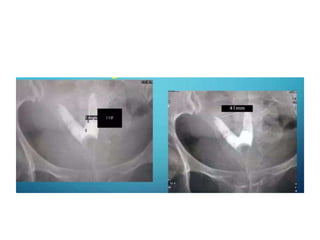

Unicornuate uterus

Bicornuate uterus

• Intercornual angle- <75

• Intercornual distance <2cm

• Intercornual angle ->105

• Intercornual distance 2-4cm

SEPTATE UTERUS • Intercornualangle- <75 • Intercornual distance <2cm BICORNUATE UTERUS • Intercornual angle ->105 • Intercornual distance 2-4cm